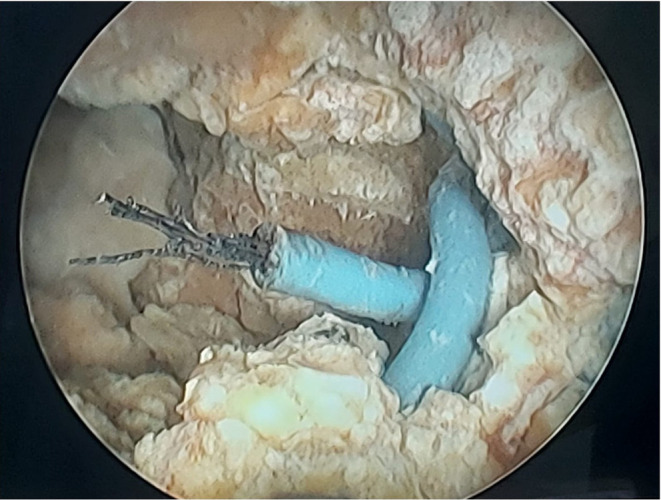

Bladder foreign bodies (BFBs) are an uncommon clinical occurrence, often resulting from trauma, self-insertion, iatrogenic causes, or organ migration. These objects can act as nidus for stone formation, leading to vesicolithiasis. Here, we present a rare case of a 61-year-old male with hematuria, dysuria, and abdominal pain. Initial evaluation, including imaging and cystoscopy, revealed a bladder stone encapsulating a foreign object identified as a blue cable wire. Despite denying self-insertion, his history suggested potential unreported trauma. Management involved cystoscopic lithotripsy and foreign body extraction. The case underscores how foreign objects act as nidus for stone formation through inflammatory and biochemical pathways, emphasizing the importance of early diagnosis and appropriate surgical management to prevent severe complications.